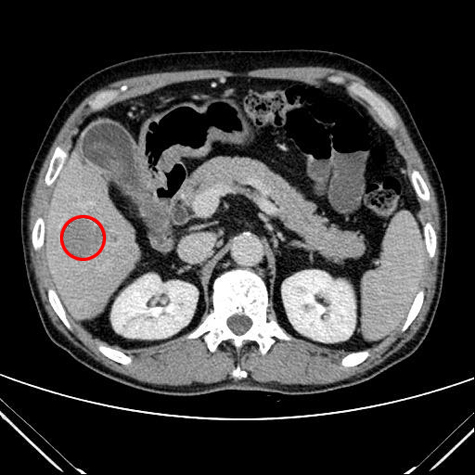

40대 남성, 초음파 검사하다 간 이상 발견

원 안이 간암 부분

간암의 생존율은 26.7%(2006-2010, 국가암등록통계)로 매우 낮은 편이지만, 발생 초기에는 진행속도가 매우 느리므로 검진을 통해 조기 발견되면 완치 확률이 높아진다.

동남권원자력의학원에서 지난 2월 간암 절제술을 받은 배00 씨(울산시 울주군, 40세)가 그런 경우이다. 배 씨가 초기 간암을 발견할 수 있었던 것은 높은 당뇨 수치 때문이었다. 배 씨는 “어느 날부터 갑자기 너무 목이 말라서 하루에 물을 4리터씩 마셔대곤 했는데, 이 증상이 보름 이상 지속되어서 병원을 찾았더니 혈당수치가 450이 넘게 나왔다. 당뇨 때문에 췌장 초음파 검사를 하던 도중, 간에 혹이 있다는 이야기를 들었다”고 밝혔다.

이후 동남권원자력의학원 암센터에서 배씨의 검사는 빠르게 진행되었다. MRI 촬영과 혈액검사 결과, 간에서 보인 2.5cm 정도의 혹이 간암으로 밝혀졌다. 수술을 집도한 소화기암센터 외과 임창섭 과장은 “B형 간염도 있어서 조금 이른 나이에 간암이 온 것으로 판단된다. 간 절제술을 시행한 후 순조롭게 회복하고, 현재 외래에서 재발여부 등에 대한 추적관찰 중이다”고 밝혔다.